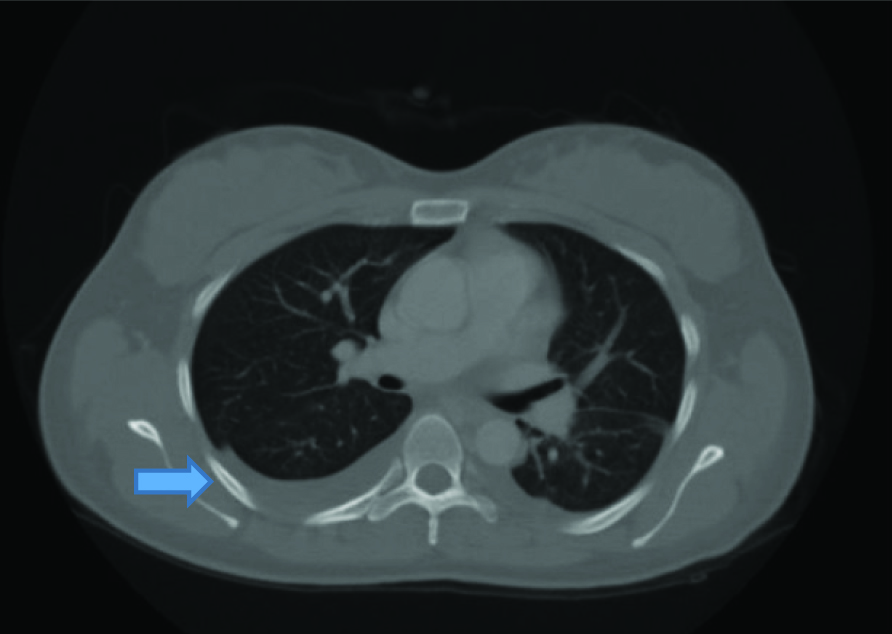

A 27-year-old primigravid female was referred to our clinic with severe preeclampsia at 35 weeks of gestation. Her medical history was uneventful. She was administered 1000 mg/day alpha-methyldopa since, 28 weeks of gestation. On admission, her blood pressure was 180/ 110 mmHg and urinary albumin 2+. Complete Blood Count (CBC) was in normal limits. Her serum biochemical analysis revealed: ALT: 401 U/L, AST: 292 U/L, creatinine: 1.39 mg/dL, urea: 40 mg/dL (16.6-48.5), uric acid: 8 mg/dL (2.4-5.7), total protein: 6.25 g/dL (6.4-8.3) and albumin: 3.3 g/dL (3.5-5.2). Her coagulation profile was within normal limits. A single live fetus of 31 weeks gestation along with 85 mm amniotic fluid index was detected by USG. Colour flow doppler USG revealed increased umbilical artery resistance. There were no subjective symptoms such as headache, epigastric pain and visual symptoms. Late decelerations were detected on cardiotocography trace and she was diagnosed to have fetal distress. An emergency cesarean section was performed and 1450 gm male fetus was delivered with APGAR score of 8/10. Postoperatively, she was given amlodipine 20 mg/day. Her blood pressure recordings were within normal limits. On first postoperative day 20-30 cc/hour urine output was detected. Serum transaminases were lowered. On the second postoperative day, she had abdominal distension and severe abdominal pain. The USG showed minimal ascites fluid. CBC was normal and serum albumin level was 2.5 gm/dl. Serum sodium level was normal. She had 320 μg albumin/mg creatinine (albumin:creatinine ratio) on spot urine sample. On the 3rd post-operative day, her abdominal distension increased and USG revealed massive ascites. Abdominal drainage was performed and albumin infusion was administered. Approximately 3000 cc serous fluid was drained. The sample analysis revealed as characteristic of transudate. Abdominal distension regressed but she had pulse of 130/min. X-ray chest showed bilateral minimal pleural effusion [Table/Fig-1]. She had normal echocardiography. Serum creatinine levels regressed (<1 mg/dL) but her urine output exceeded 500 cc/hour. IV hydration was adjusted as less than 1000 cc of total daily urine output. On post-operative day 4, she still had abdominal distension and concomitant respiratory distress. Computed Tomography showed bilateral pleural effusion and minimal ascites and atrophic right kidney [Table/Fig-2,3]. In spite of increased urine output her sodium level remained within normal levels. There was no proteinuria in spot urine sample. On post-operative day 5, she had total of 3000 cc/day hydration and 5000 cc/day urine output. Her complaint regressed on the following days and on post-operative day 7 USG showed no ascites and gap between input and output disappeared. She was discharged on postoperative day 10.

Computed tomography, bilateral pleural effusion and minimal ascites.